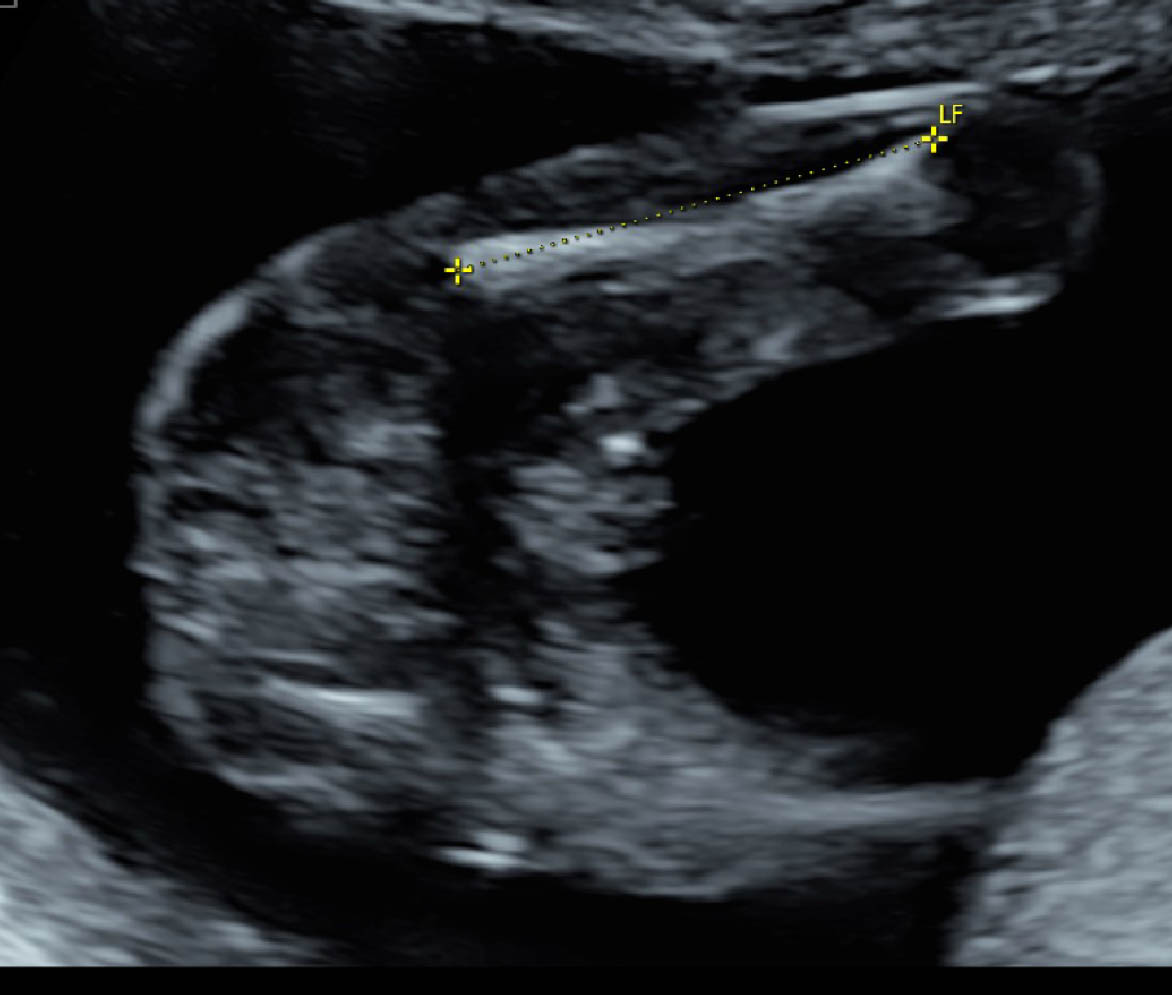

This is my baby's ultrasound at 17 weeks. The doctor didn't want to reveal the gender yet (said she's not 100% sure). I don't know if these are good gender shots, but what would you say?